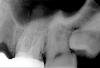

dok1 Опубликовано 10 января, 2013 Поделиться Опубликовано 10 января, 2013 В принципе Вы изложили все аргументы. На снимках видны неточности конструкций. Вот так и ведите диалог. Ссылка на комментарий